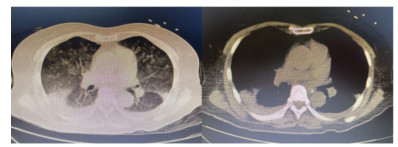

1 资料与方法患者,女,64岁,居住农村,既往有糖耐量异常5年,未正规治疗,4年前诊断为“原发性甲状腺功能亢进”,经治疗已好转。无高风险、中风险地区旅居史,无境外旅居史,无新冠病毒肺炎确诊或疑似患者接触史。2020年7月31日患者无明显诱因下在家中出现发热,体温最高39.4 ℃,伴畏寒、全身乏力,无胸闷、胸痛,无咳嗽、咳痰,无腹痛、腹泻,无黑矇、晕厥,遂在家中自服“退热药”后体温降至正常,但体温仍有反复。8月2日早晨患者再次出现发热,伴畏寒、寒战,遂至本院发热门诊就诊,予查C-反应蛋白156 mg/L,降钙素原0.64 ng/L,考虑感染性发热,遂予“哌拉西林他唑巴坦钠4.5 g每12 h一次”静滴抗感染治疗,后患者突发呼吸费力,伴咳嗽、咯血,为鲜红色血液,量较多,遂于8月2日14:18送达本院急诊抢救室。来时患者呼吸急促,有咳嗽伴咳血性痰,双侧小腿持续性钝痛,查体:血压188/86 mmHg(1 mmHg=0.133 kPa),心率168次/min,呼吸36次/min,血氧饱和度50%,体温38.6 ℃。神志清,精神软,急性面容,双侧结膜略充血,全身皮肤黏膜未见明显充血、淤血,未触及淋巴结肿大。口唇微绀,两肺呼吸音粗,可闻及明显湿性啰音,心律齐,无明显病理性杂音;腹平软,无压痛反跳痛,四肢肌力Ⅴ级,两侧病理征未引出。予心电监护、特级护理、面罩吸氧、建立静脉通道,送检血常规、生化、血气、心肌酶、凝血酶原时间系列、痰培养等常规检查,同时予送检血标本行高通量测序,完善胸部CT检查(图 1)。辅助检查结果如下:8月2日胸腹部CT示两肺感染,腹部未见明显异常。血常规:白细胞计数7.9×109/L,中性粒细胞百分比89%,血红蛋白121 g/L,血小板计数104×109/L,C-反应蛋白156.82 mg/L。血生化:丙氨酸氨基转移酶51 U/L,天门冬氨酸氨基转移酶63 U/L,白蛋白34.5 g/L,总胆红素17.4 mmol/L,肌酐74 mol/L。心肌酶谱:心肌肌钙蛋白I 0.014 ng/mL,肌红蛋白322 ng/mL,肌酸激酶同工酶3.2 ng/mL。血气分析:pH 7.435,二氧化碳分压29 mmHg,氧分压53.5 mmHg,K+ 2.6 mmol/L,Na+ 132 mmol/L,血乳酸3.1 mmol/L。新型冠状病毒抗体、核酸阴性。接诊医师初步诊断为“咯血待查:疑似肺部感染,呼吸衰竭”,治疗上予亚胺培南0.5 g静滴经验性抗感染、甲泼尼龙80 mg静滴抗炎,同时予化痰、平喘等对症、支持。17:00患者出现呼吸费力加重,10 L/min面罩吸氧下血氧饱和度仍为70%,故予紧急气管插管、机械通气,随后转入ICU,联系感染科医师会诊,结合患者病史及CT影像学表现的广泛、片状密度增高影特点,考虑钩端螺旋体病可能性大,不排除“赫氏反应”,故继续予亚胺培南0.5 g静滴每6 h一次抗感染、甲泼尼龙80 mg静滴每12 h一次抗炎、白蛋白营养支持等治疗。8月3日更改甲泼尼龙80 mg静滴每天一次。8月4日高通基因测序回报:检测出问号钩端螺旋体DNA,符合入院时推断,明确病原体后予修正诊断为肺出血型钩体病伴赫氏反应。8月5日停亚胺培南,改青霉素160万单位静滴每8 h一次。8月8日患者病情稳定,拔除气管导管,予甲泼尼龙减量为40 mg静滴1次/d,8月9日复查胸部CT提示两肺斑片状、片状密度增高影较前有所吸收(图 2),停用甲泼尼龙。8月10日转入呼吸科。8月17日复查胸部CT提示两肺斑片状、片状、条索状密度增高影,较前明显吸收(图 3)。8月20日患者好转出院。9月18日随访,复查CT提示两肺散在条索状密度增高影,基本恢复正常(图 4)。

| 图 4 9月18日患者随访时胸部CT示两肺散在条索状密度增高影,基本恢复正常 |